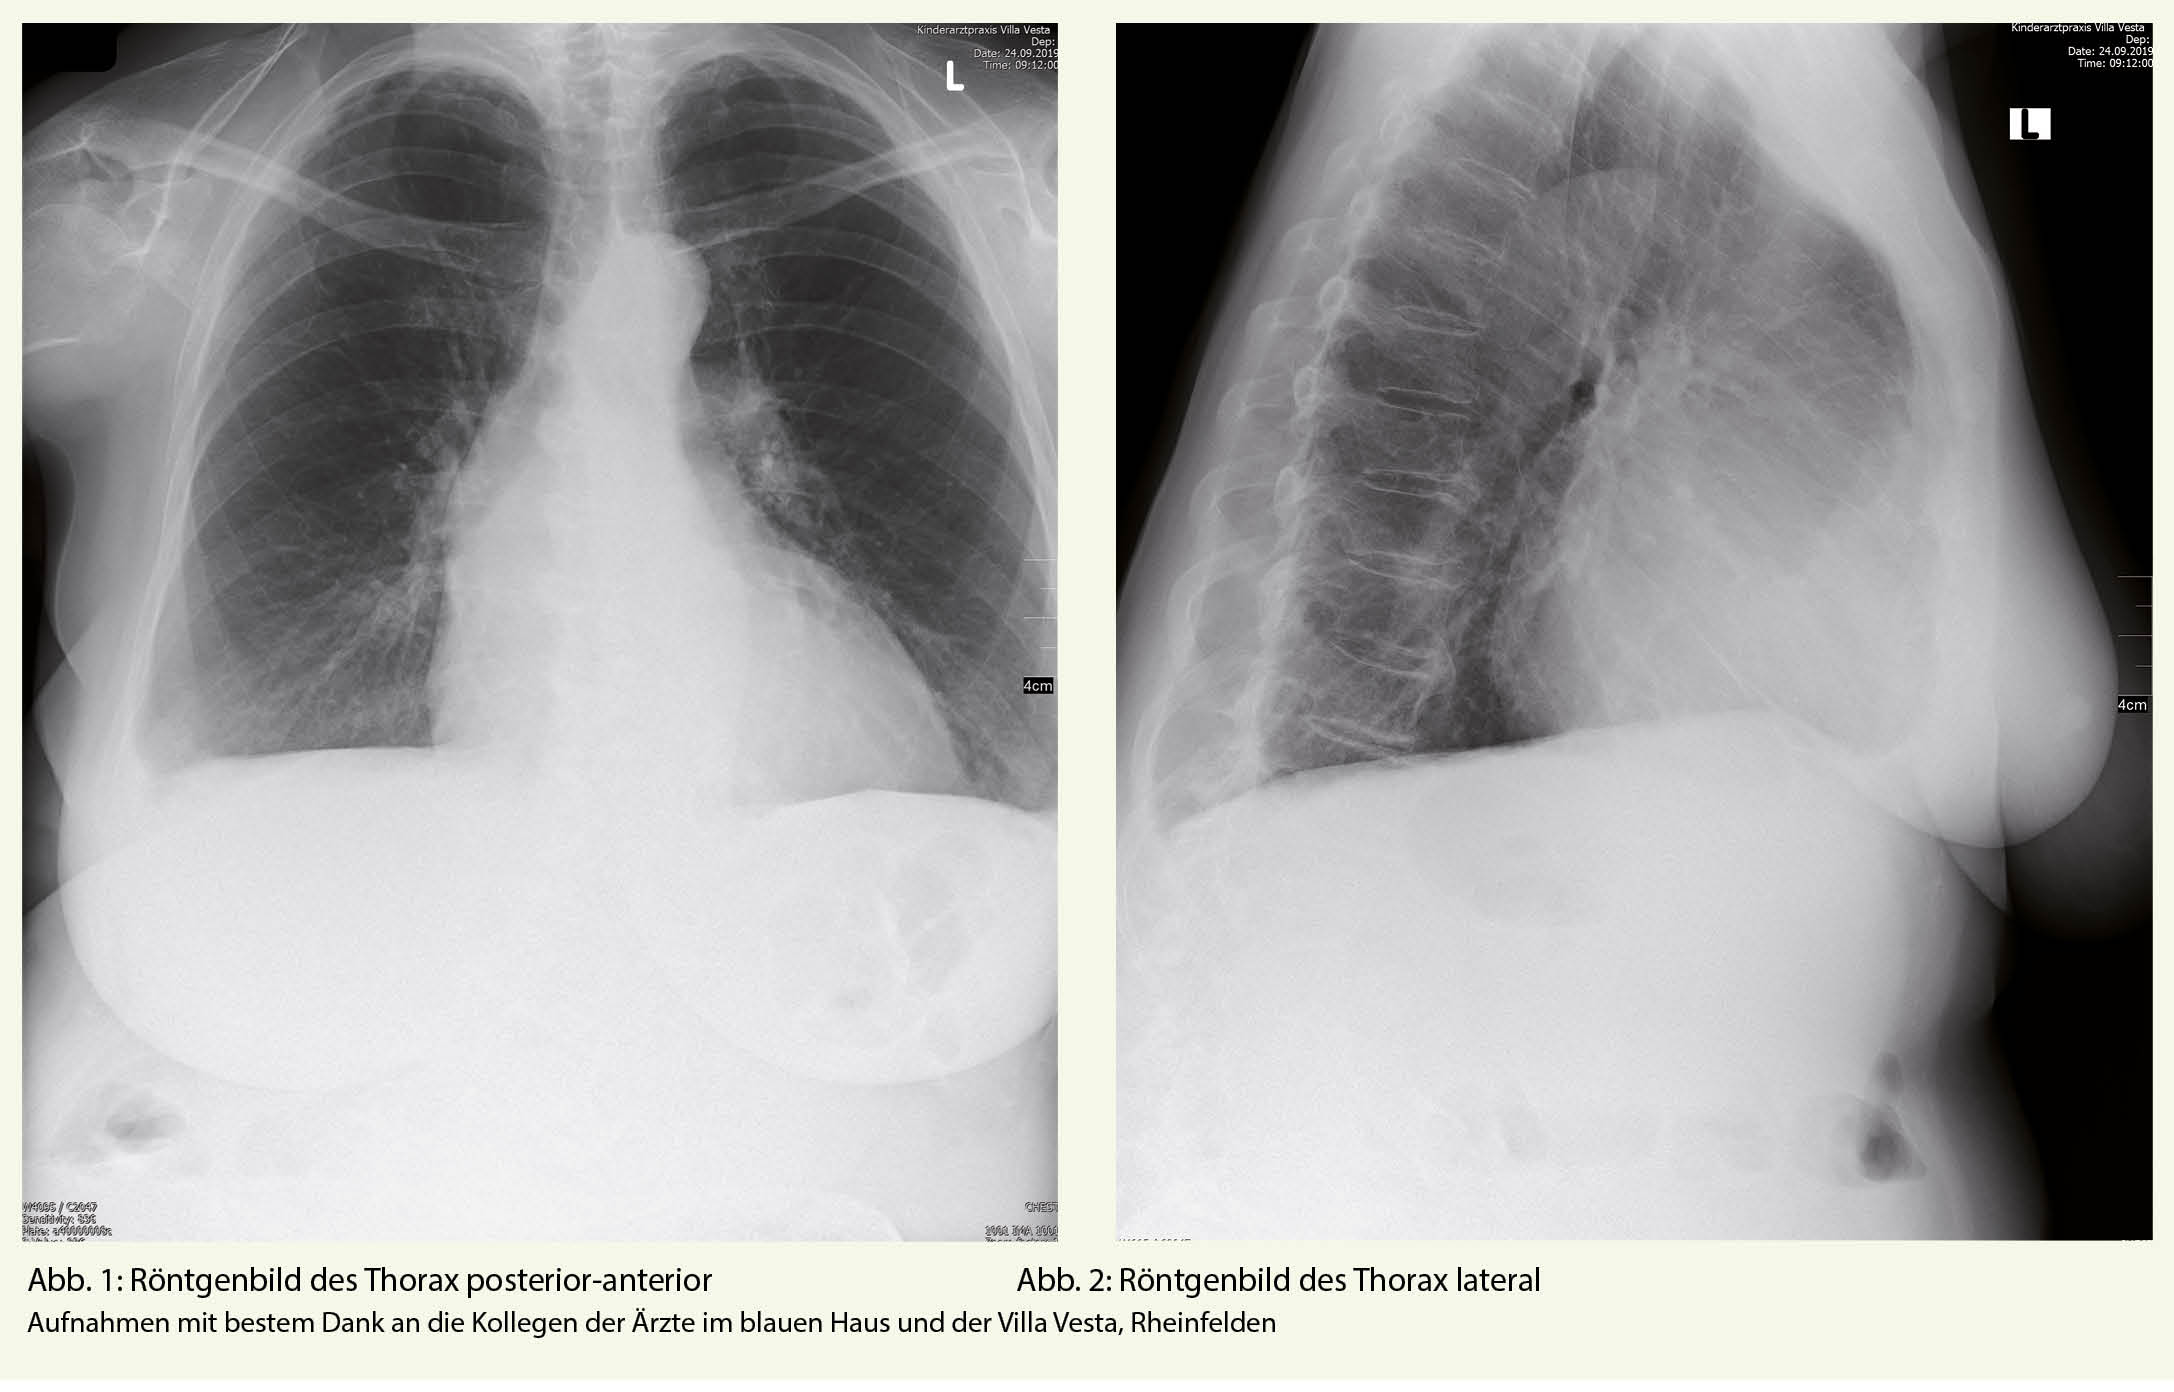

Im konventionellen Röntgenbild des Thorax ist bei nicht optimaler Aufnahme ein leichter Erguss rechts basal sowie eine basale, streifige Mehrzeichnung aber kein eindeutiges, pneumonisches Infiltrat feststellbar. Das Mediastinum ist mittelständig und klar abgrenzbar. Auch die Herzgrösse erscheint physiologisch.

Die konventionelle Röntgenaufnahme wird aufgrund der Symptomkonstellation häufig durchgeführt, besitzt zur Diagnose einer akuten Aortendissektion eine jedoch nur geringe Sensitivität und Spezifität (4). Ein erweitertes Mediastinum, Deviation der Trachea und besonders ein linksseitiger Pleuraerguss, sollten differentialdiagnostisch immer auch an eine akute Aortendissektion denken lassen (1).